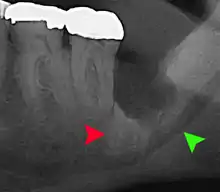

Coronectomy is a procedure where the crown of the impacted wisdom tooth is removed, but the roots are intentionally left in place. It is indicated when there is no disease of the dental pulp or infection around the crown of the tooth, and there is a high risk of inferior alveolar nerve injury.[31]

Coronectomy, while lessening the immediate risk to the inferior alveolar nerve function has its own complication rates and can result in repeated surgeries. Between 2.3% and 38.3% of roots loosen during the procedure and need to be removed and up to 4.9% of cases require reoperation due to persistent pain, root exposure or persistent infection. The roots have also been reported to migrate in 13.2% to 85.9% of cases.[31]